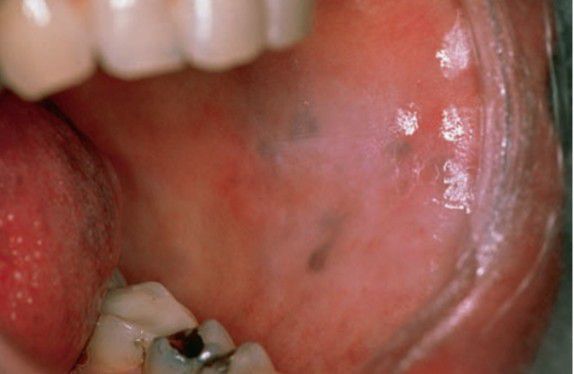

Drug induced pigmentation

This clinical picture shows cyclophosphamide induced pigmentation of buccal mucosa